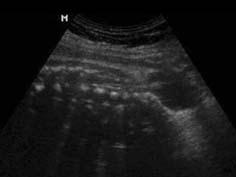

问题 25岁孕妇,孕37周,行产前常规超声检查,既往体健,超声发现如下图所示,根据图像最有可能诊断为 ( )

选项 A、无脑儿 B、以上都不是 C、脐带绕颈 D、脊膜膨出 E、脊柱裂

答案 E